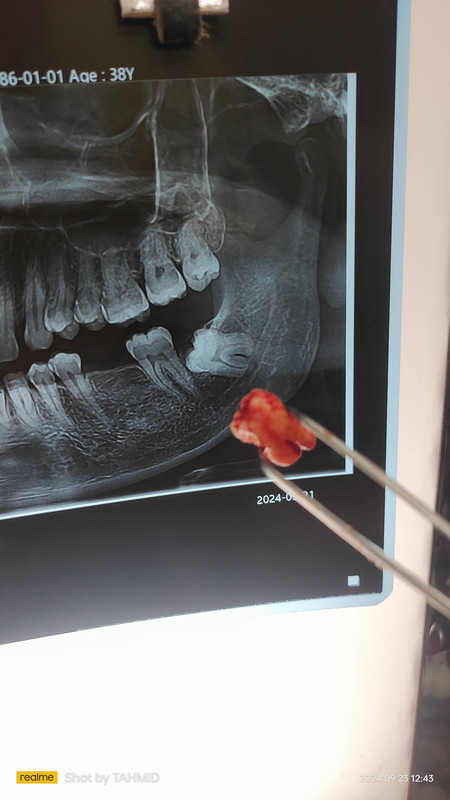

Single Layer জিরকোনিয়া

মাল্টি লেয়ার জিরকোনিয়া

দাঁতের প্রাকৃতিক গঠন বজায় রেখে শক্তিশালী ক্রাউন স্থাপন।

৩৮ বছর

১৫ বছর ওয়ারেন্টি